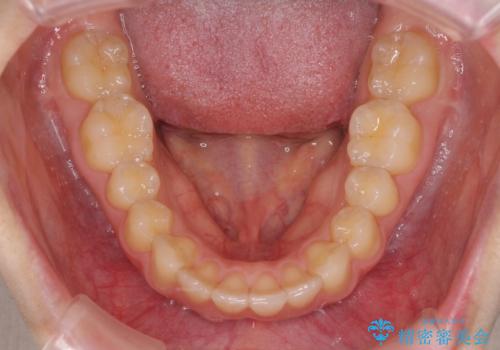

就職前にきれいな歯並びにしたい 大学生のインビザライン矯正

- 就職するまでに歯並びをきれいにしたいとのことで来院された患者様です。

前歯の叢生を気にしていましたが、極力突出感を改善できるようにすることとし、インビザラインにて矯正治療を行うこととしました。

改善の期待できない口元の突出感改善を希望されたため、いたずらに治療期間が延びましたが、きっちりと仕上がりました。